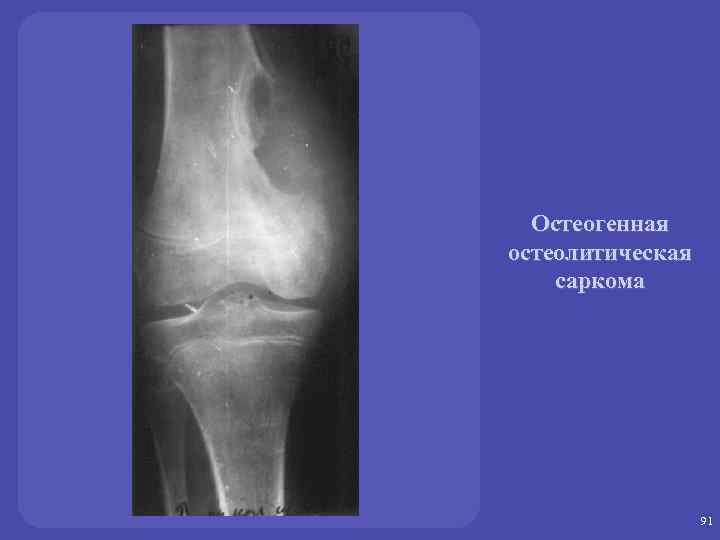

Метастазы в кости: Рентгеновские снимки и диагностика